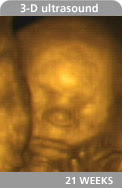

not baby O; just so you can see it really is a REAL baby in there :)

During my ultrasound last week they estimated baby O at 14 oz; heartrate was 156. To read more about that appointment and see pics, go HERE. I actually have another appointment next Tuesday and will have another ultrasound in about 3 weeks.